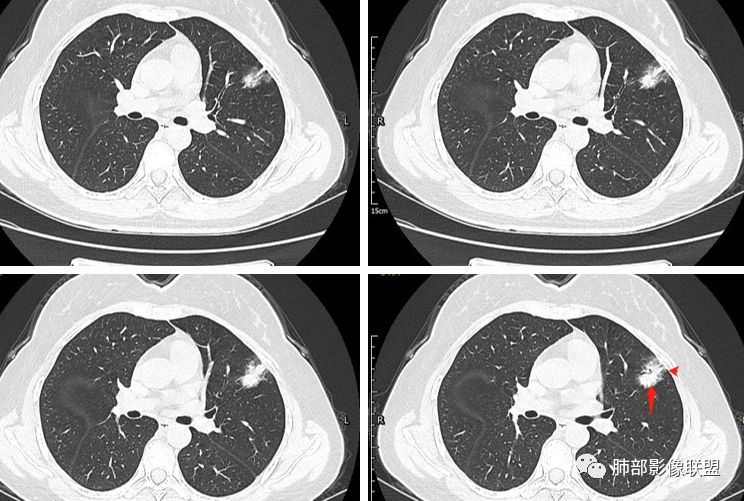

分叶结节,内部结构杂乱,边缘板刷样毛刺,GGO边界清楚

胸膜牵拉

月牙铲?

常规要考虑腺癌

2.病灶的胸膜牵拉线与其间病灶胸膜侧的磨玻璃边构成朝向胸壁的“月牙铲”结构,这种影像学表现某种程度上反映出病理学特征——病灶收缩+小叶间隔阻挡。

在影像上观察到肿块或磨玻璃结节一侧的内凹,像个月牙铲形态,病理是肿瘤生长受到小叶间隔阻挡并受肿瘤内部的收缩力形成,王兆宇老师称之为“月牙铲”!对诊断肺腺癌较有特异性。